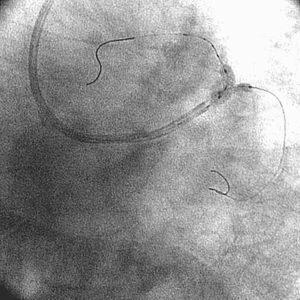

どうしようかとホトホト悩みましたが、スネアなど当然カテ室にはないので、ワイヤ

2本を取り出し、絡めようとしました(fig5)。最初はうまく回収できず、この操作

中、漂流したワイヤ先端は、LCx末梢に落ちたので(fig6)、もうそのままにしようか

なあ、とも思ったのですが、あきらめず、さらに根性を出して、今度はワイヤ3本を

横にとおし、(シネにはとっていませんが)絡めてみると取り出すことができまし

た。証拠写真(fig7)です。本当に、ホッとしました。そのあと、long-tipを出して

PCIしたら、(当然)あっさり、バルーンは通り、5分もかからず終了しました(fig

8)。